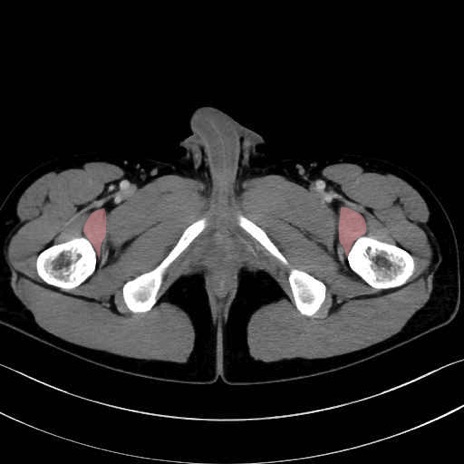

大腿方形筋 (Quadratus femoris)